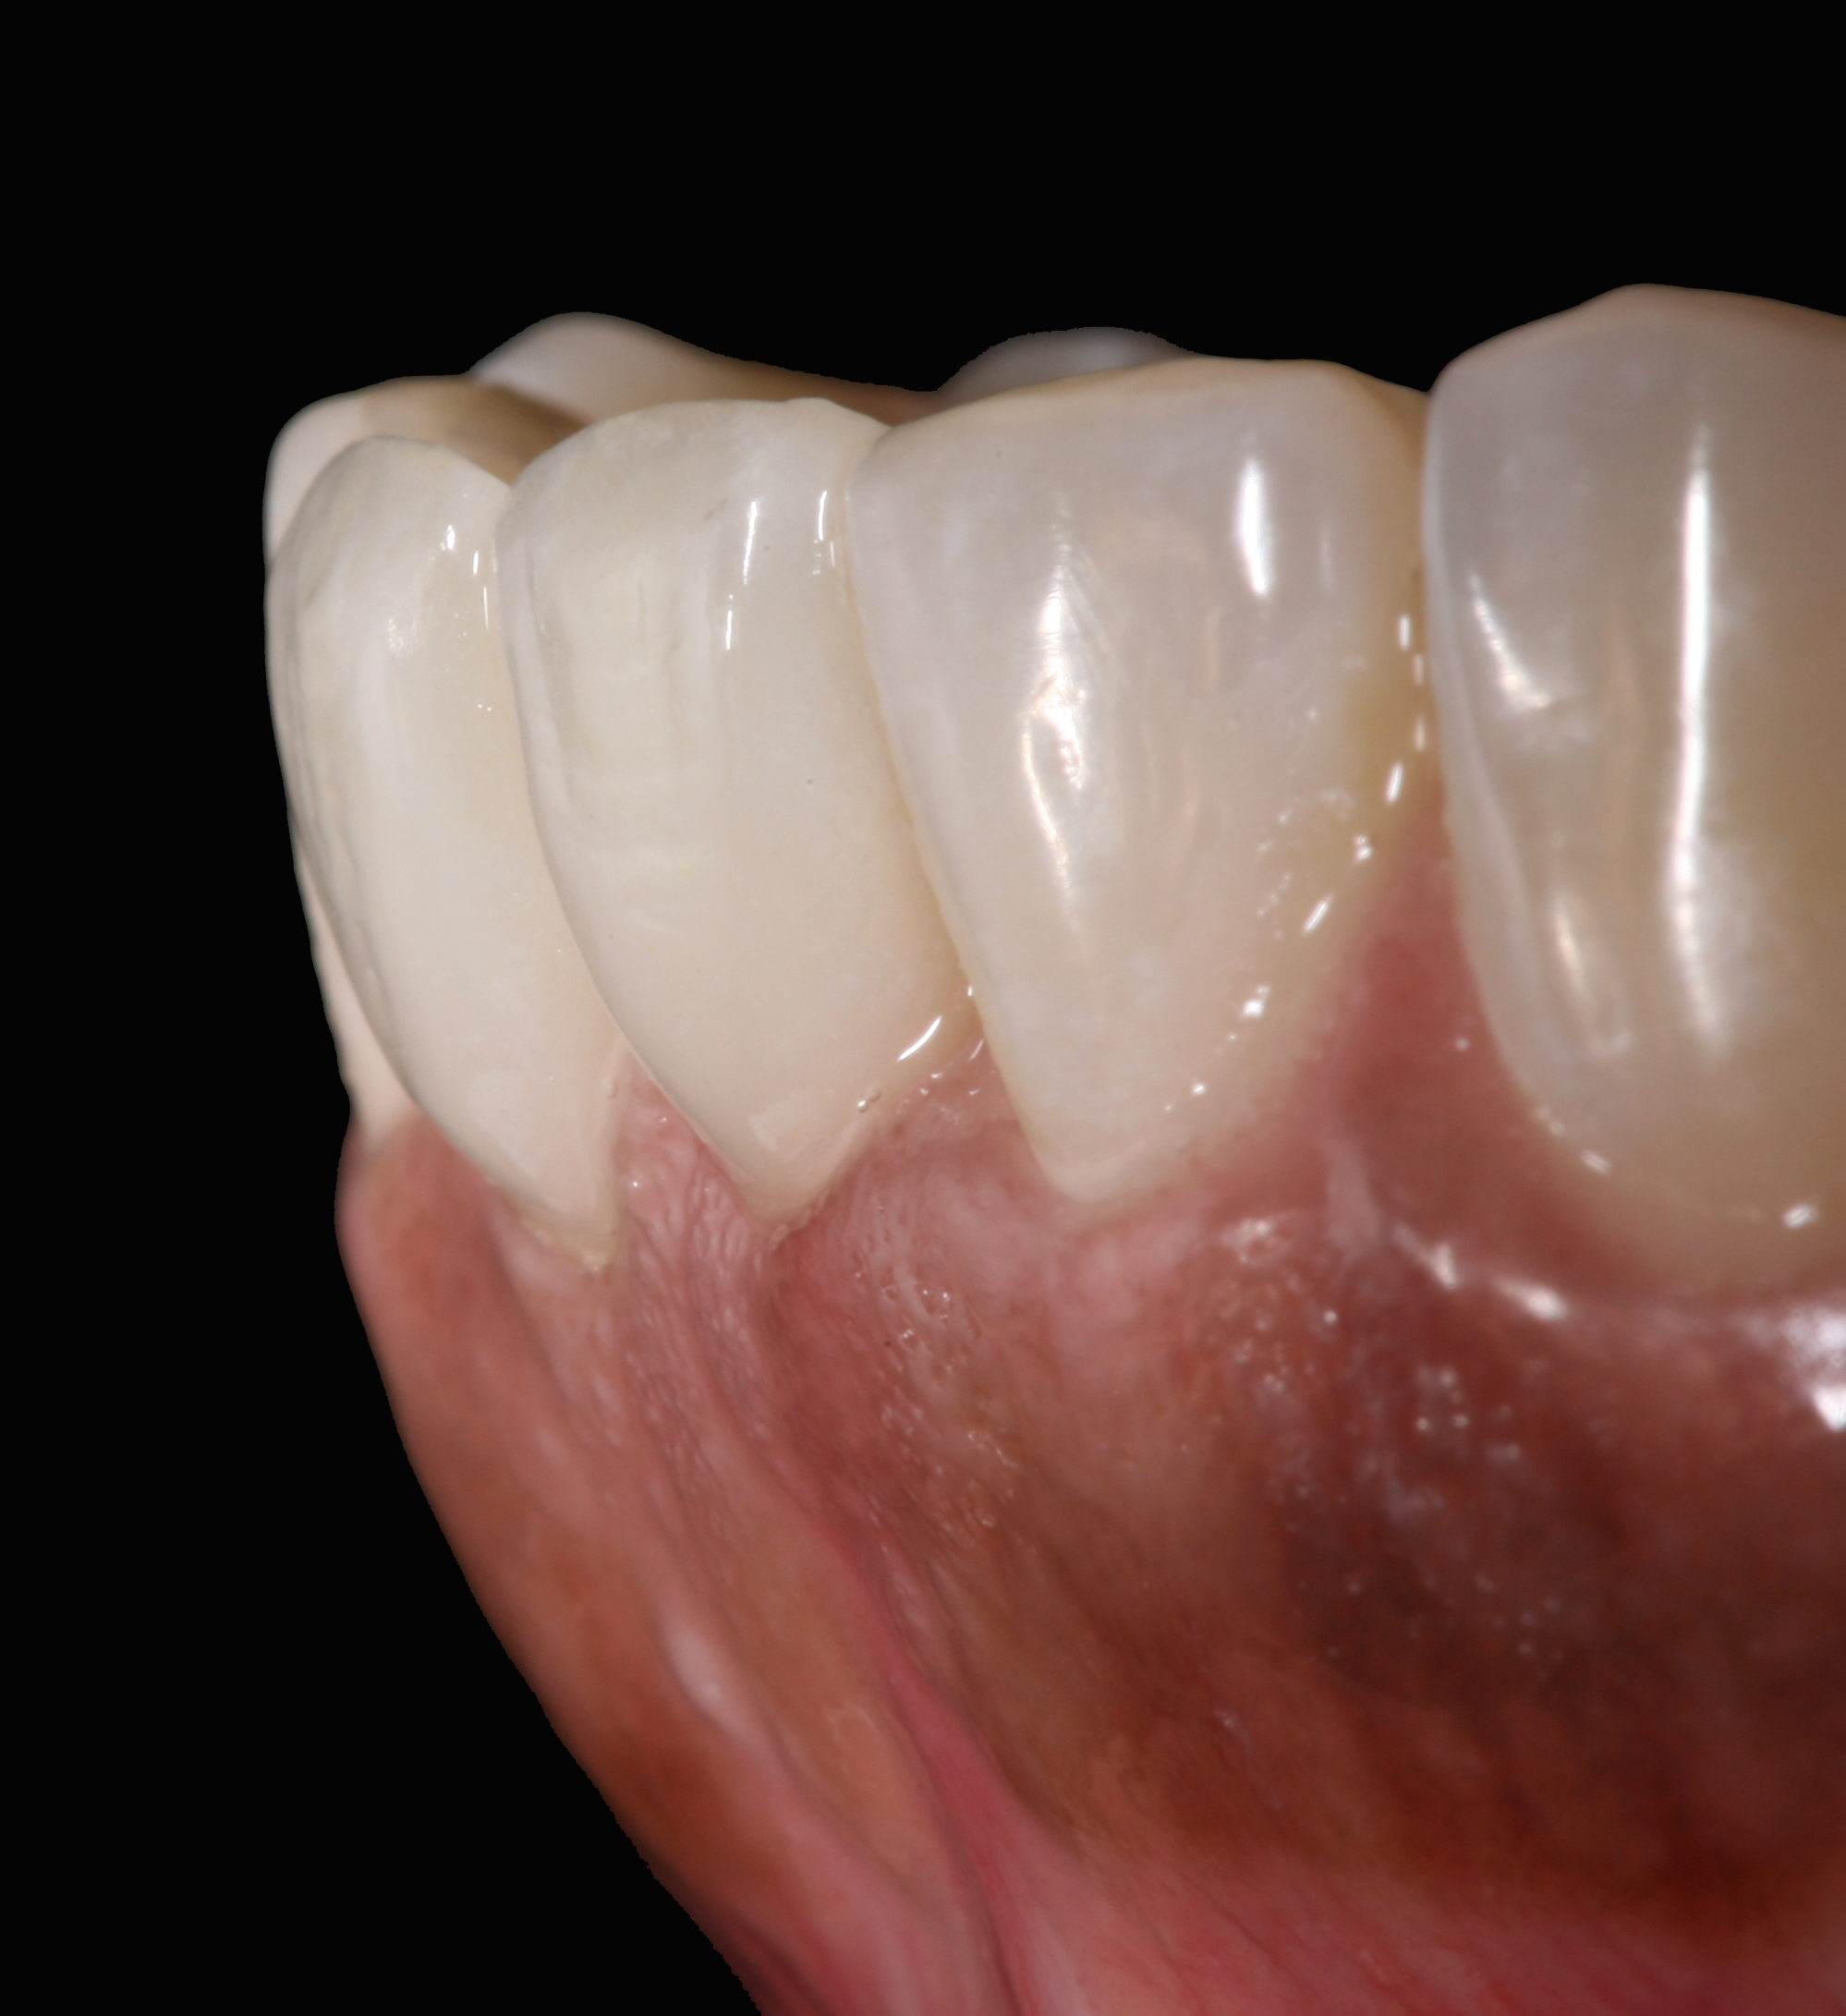

The clinical application of this protocol is illustrated in a patient situation where laminate veneers were placed on four maxillary incisors to replace lost tooth structure and restore function and esthetics. The failing restorations were removed, followed by a conservative veneer preparation (Figure 1 and Figure 2). The bonding surfaces of the feldspathic porcelain veneers were acid-etched with hydrofluoric acid for 2 minutes (Figure 3) and thoroughly rinsed. Then a silane coupling agent was applied (Figure 4). Figure 5 demonstrates the situation after bonding the veneers to the teeth with a composite resin luting agent.

Postoperative situation: left lateral view.

Figure 11

Postoperative situation: right lateral view.

Figure 12